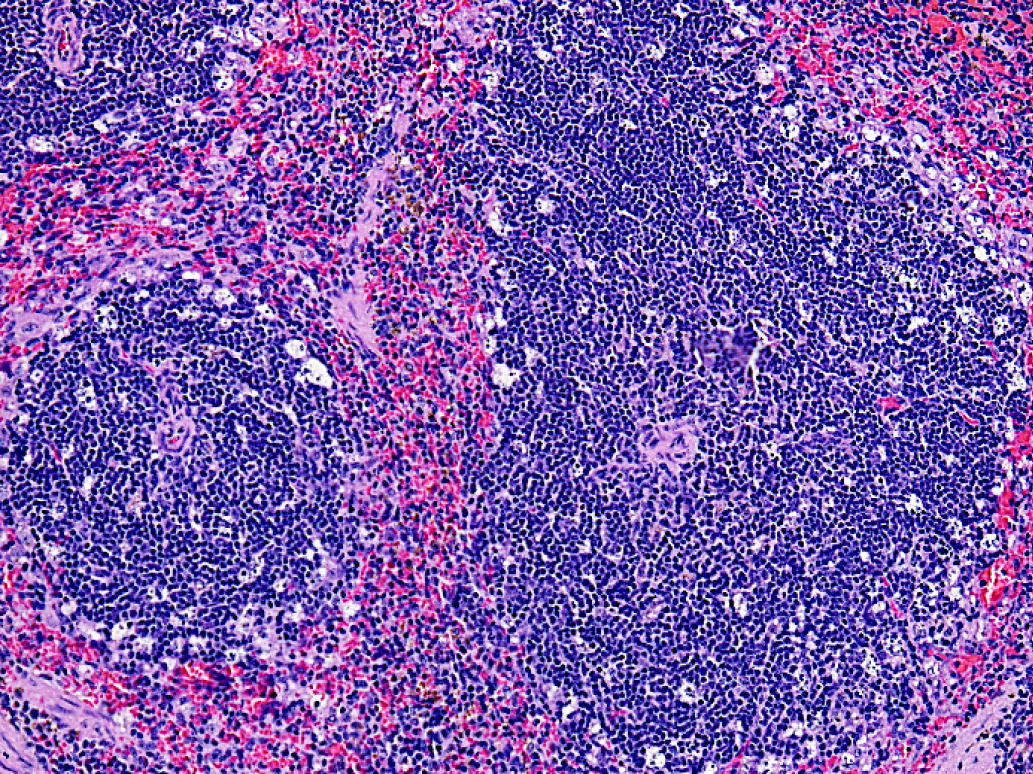

В селезенке подопытных животных регистрировали многочисленную гибель лимфоидных клеток по периферии фолликулов белой пульпы (рис. 4).

Рис. 4. Фрагмент селезенки подопытной мыши после введения 5'- нораристеромицина в дозе 80 мг/кг. Окраска гематоксилином-эозином. Увеличение 200

5. Рис. 4. Фрагмент селезенки подопытной мыши после введения 5ˊ- нораристеромицина в дозе 80 мг/кг. Окраска гематоксилином-эозином. Увеличение 200